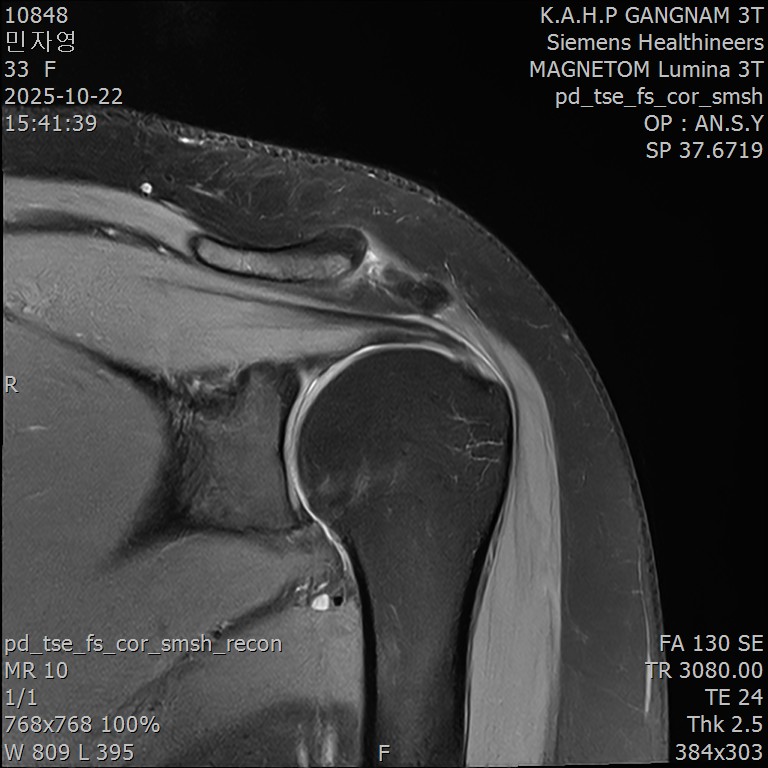

환자분의 말씀에는 체념이 묻어 있었습니다. MRI를 가져오셨는데, 판독 소견에는 "경미한 퇴행성 변화 외 특이 소견 없음"이라고 적혀 있었습니다.

MRI는 정상인데, 왜 오십견이 반복되는 걸까요?

회전근개 힘줄 사이사이에 미세한 석회 침착이 여러 군데 흩어져 있었습니다. 크기가 매우 작아서 3mm 단위로 단면을 촬영하는 MRI에서는 보이지 않았지만, 초음파로는 선명하게 확인되었습니다.